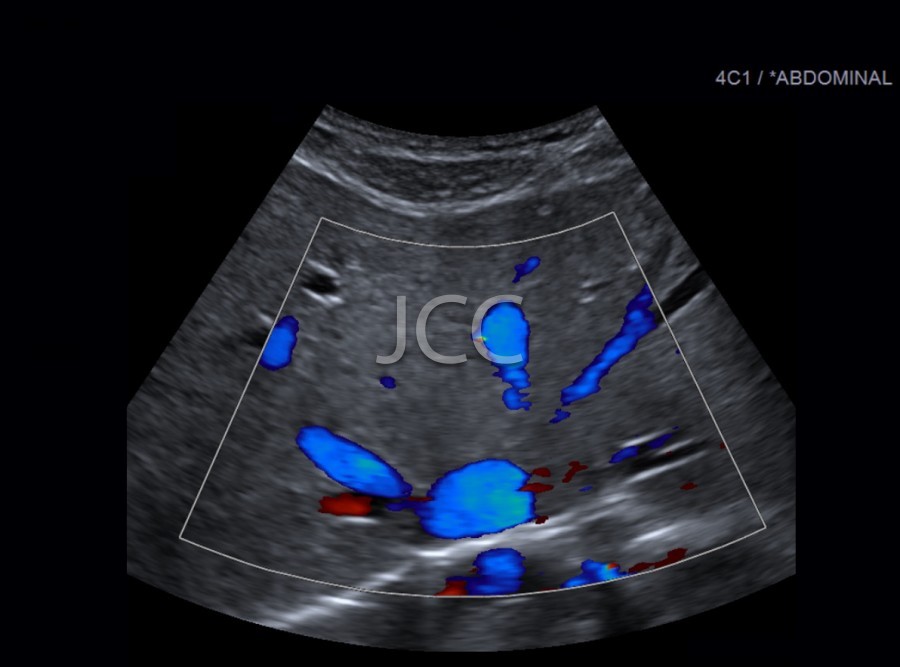

Ecografia - Ecografia Vascular - Doppler

A Ecografia constitui um método mais acessível permitindo de modo simples e rápido a avaliação dos órgãos do corpo humano incluindo o fígado, vias biliares, vesícula, pâncreas, rins, bexiga e próstata, bem como órgãos de menores dimensões como a tiróide, parótidas e estruturas musculares.

Constitui uma óptima técnica para guiar a realização de biópsia. Quando associada ao Doppler permite o estudo das estruturas vasculares arteriais e venosas de modo dinâmico.